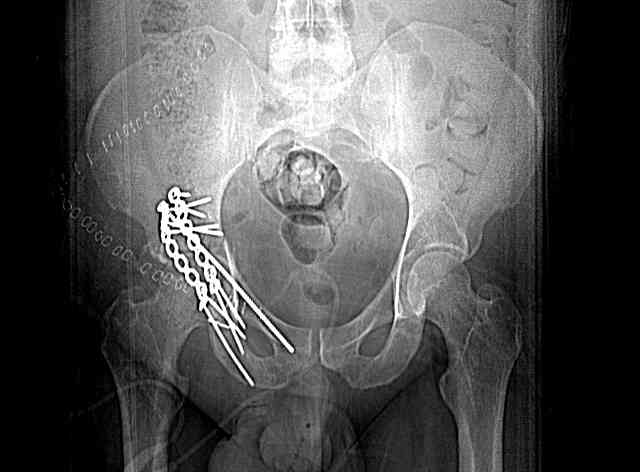

Screw Fixation

-AC Screw

-PC Screw

For Alex... here are some cannulated and 7mm screws for you... notice the fracture malreduction as indicated by the head subluxation on both views...this was a percutaneous technique without open reduction... I don¹t like it but there it is... the fixation technique is not at fault, because there was no open reduction of the fracture... but let¹s not get in to all that.